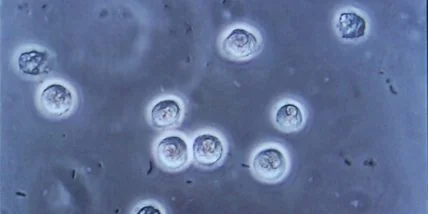

Ученые впервые сняли на видео смерть лейкоцита.

Австралийские ученые впервые записали на видео все этапы смерти лейкоцита (белой кровяной клетки) человека. Только благодаря видеосъемке биологи выяснили, что умирающие клетки пытаются послать сигнал бедствия своим коллегам по иммунной системе. Ученые рассказали об открытии на страницах журнала Nature Communications, а коротко о нем сообщает The Guardian, пишет Lenta.ru

Сотрудники мельбурнского университета Ла Троуб воспользовались таймлапс-микроскопией: замедленной покадровой съемкой (несколько сот снимков в секунду) медленно протекающих процессов с последующим просмотром на высокой скорости.

Раньше ученые были уверены, что смерть и распад клеток - это случайный процесс. Видео же продемонстрировало высокий уровень запланированности клеточной смерти. Биологи обнаружили три этапа этого процесса: вздутие, взрыв и распад. "На начальных стадиях умирания клетка начинает образовывать выступы. При взрыве же во все стороны выступают ответвления, похожие на ожерелье, которое потом распадается на отдельные "бусинки". Окружающие клетки с легкостью поглощают эти фрагменты. Но, скорее всего, в "бусинках" есть определенные молекулы - если их съест живая клетка, они посылают сигнал другим лейкоцитам: осторожно, вам также угрожает патогенный микроорганизм", - рассказала соавтор статьи Джорджия Аткин-Смит (Georgia Atkin-Smith).

Эти "ожерелья" ученые окрестили "бусообразными апоптодиями". Их длина в восемь раз превышает длину исходной клетки, а относительно их функций биологи не пришли к единому мнению. Это может быть как и инструмент предупреждения соседних клеток о наступлении опасной инфекции, так и механизм, ускоряющий распространение патогенных микробов и вирусов по организму.